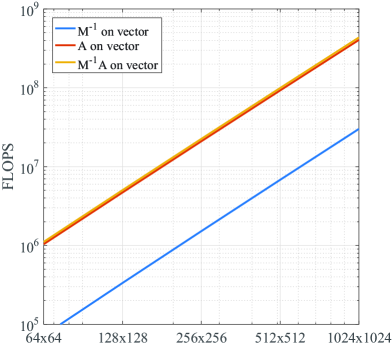

where is the approximate solution constructed by the PCG algorithm. In PCG this implies that for every iteration the preconditioner should be applied once on the residual vector . The preconditioner can be constructed beforehand since it remains fixed for the entire Split Bregman algorithm as the parameters , , and are constant. As can be seen in Table 1, is constructed in FLOPS only. Evaluation of the diagonal preconditioner from Eq. (8) on a vector amounts to two Fourier transforms and a single multiplication, and therefore requires FLOPS.

To put this into perspective, evaluation of matrix on a vector requires FLOPS, as shown in Table 1. The upper bound on the additional costs per iteration relative to the costs for evaluating on a vector is therefore

showing that the preconditioner evaluation step becomes relatively cheaper for an increasing number of coil elements. The scaling of the complexity with respect to the problem size is depicted in Fig. 1 for a fixed number of coils .